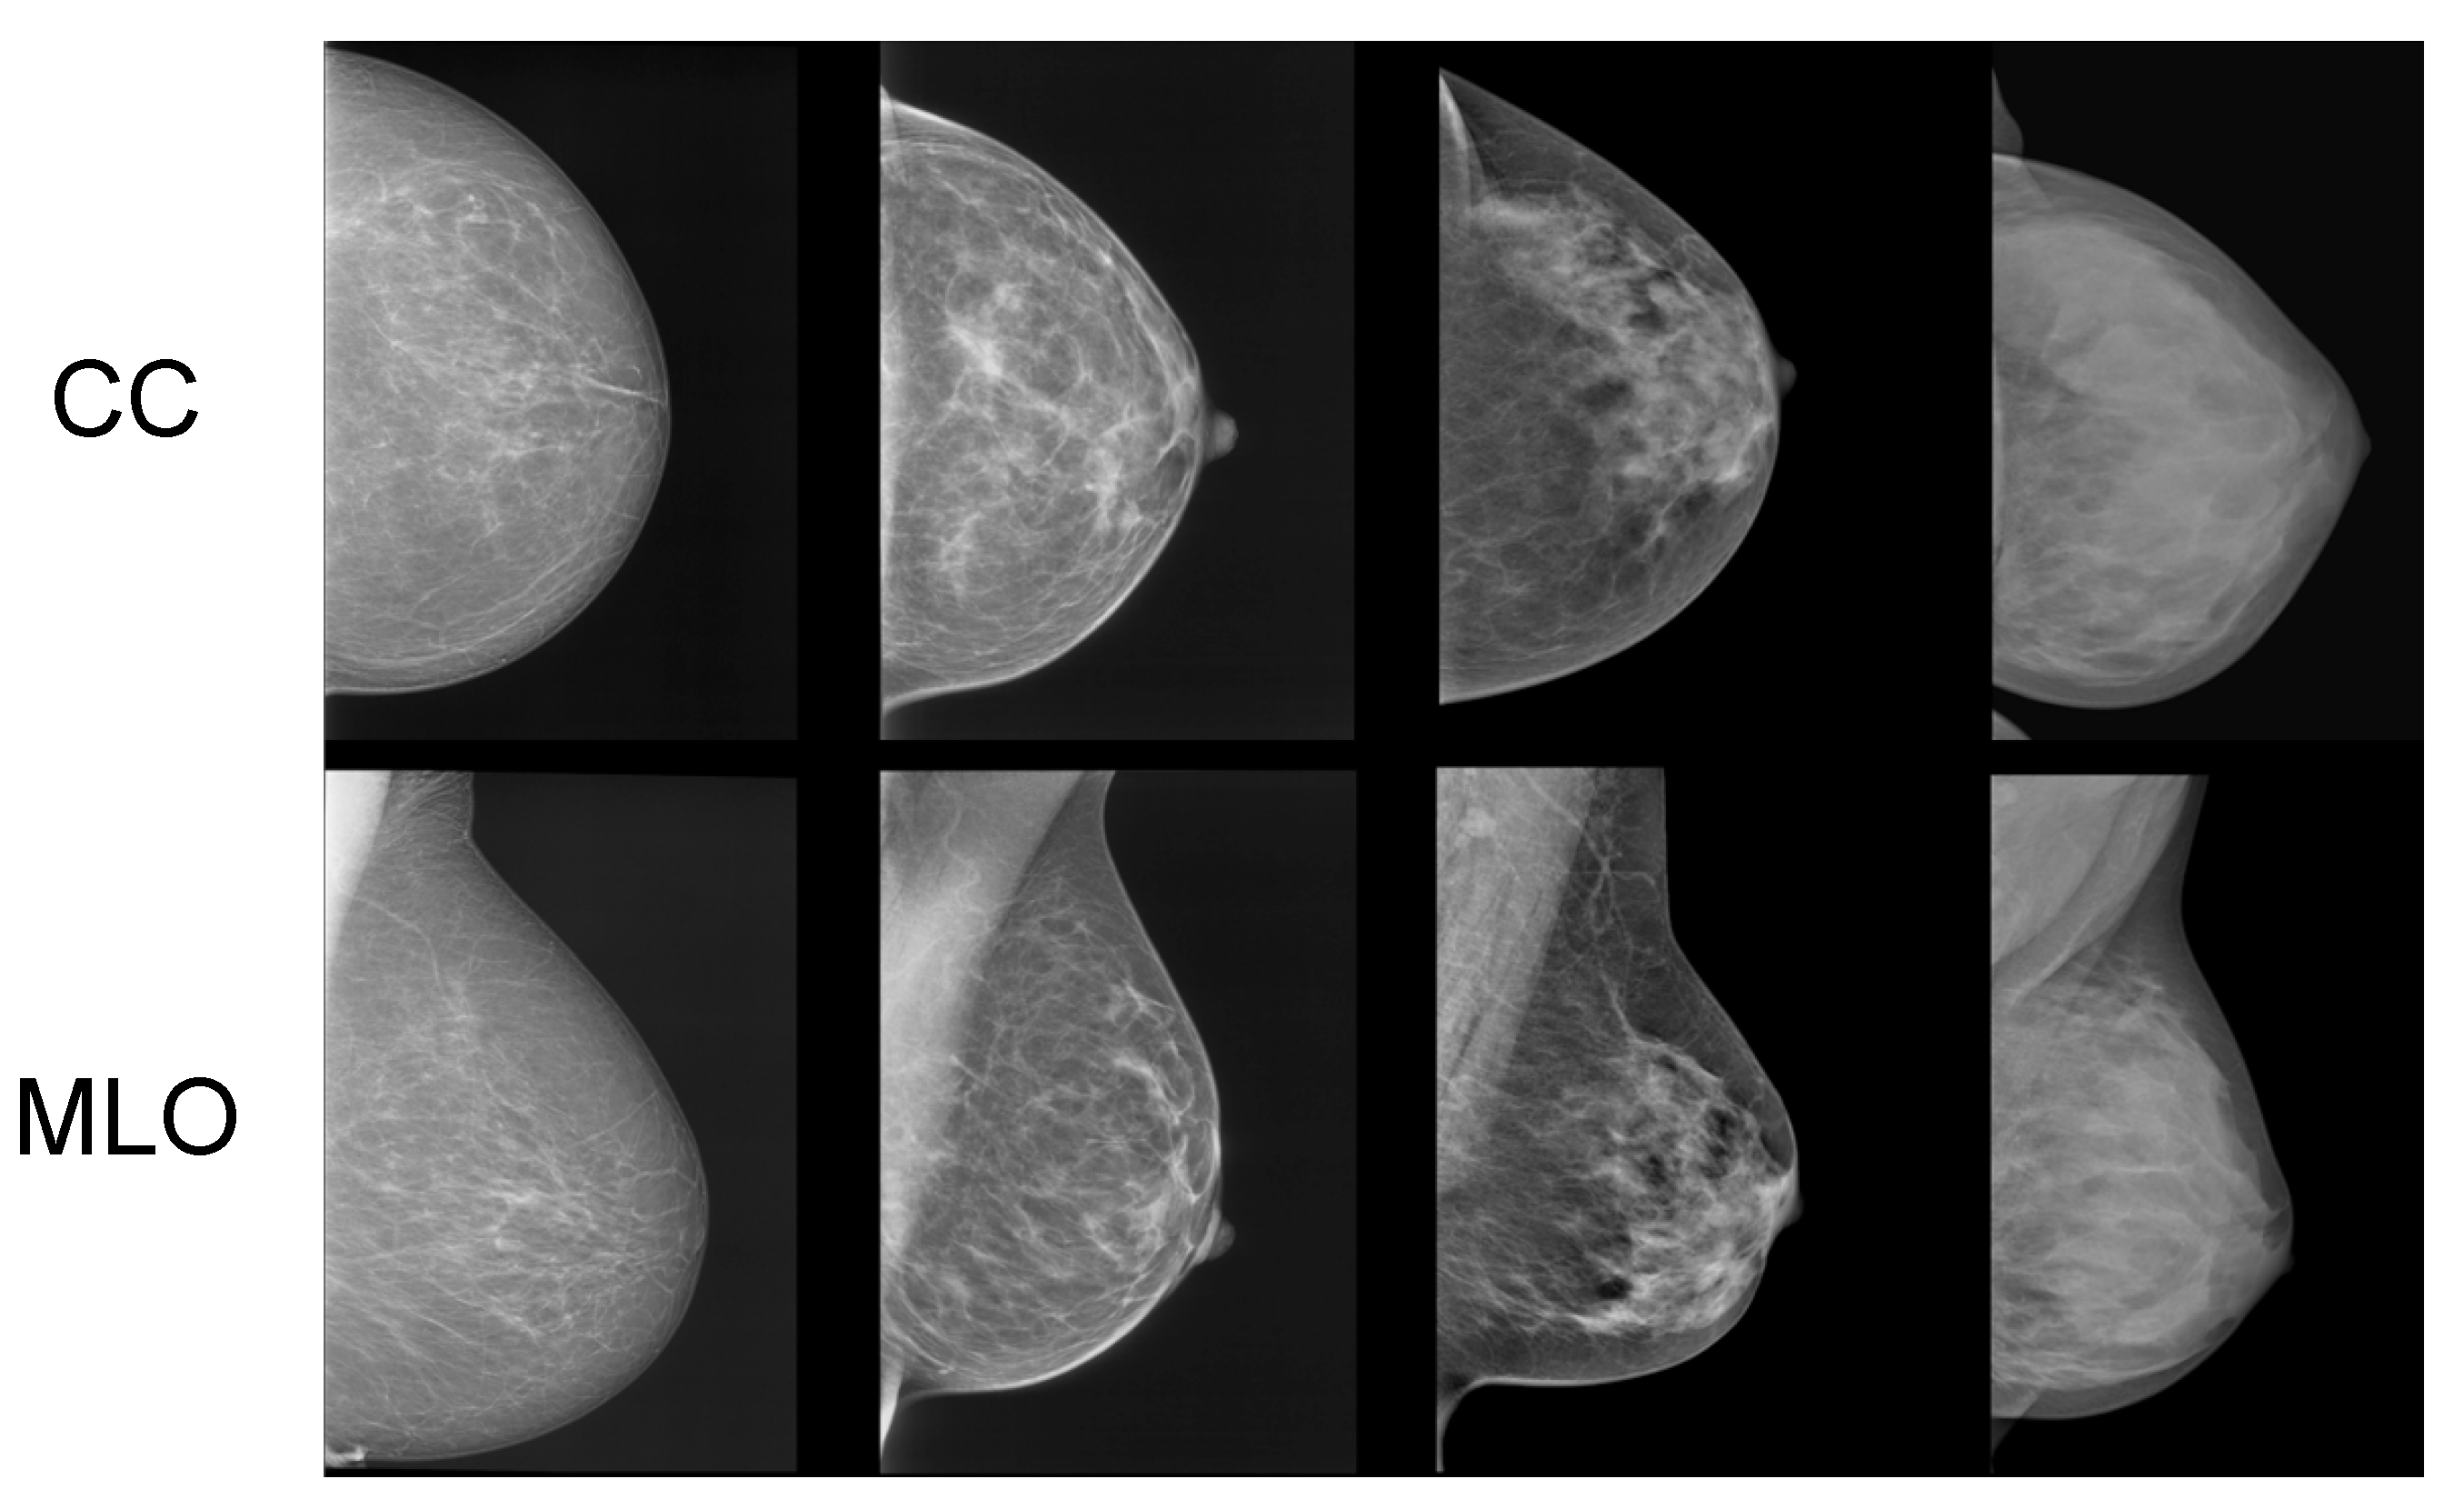

In Figure 1, samples of mammograms with varying densities are provided. Denser tissue appears light within a mammogram, contrasting with the dark appearance of fatty tissue [5]. Potentially harmful growths and tumors also appear light within mammograms. While this contrast makes it easier for radiologists to identify tumors in low-density (fatty) breasts, it notably reduces the sensitivity of mammograms in cases of highly dense breasts [6]. This is because dense tissue can mask potential tumors [6].

Figure 1.

Samples of craniocaudal (CC) and mediolateral oblique (MLO) view mammograms with differing densities [7].